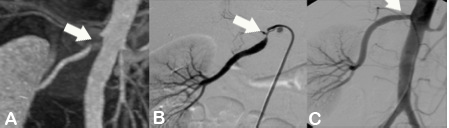

Abbildung A zeigt eine CT Angiographie der rechten Nierenarterie bei einer jungen Patientin mit schlecht einstellbarem Bluthochdruck. Die CTA zeigt deutlich eine hochgradige Abgangsstenose der rechten Nierenarterie (Pfeil). Anhand dieser CT Angiographie wurde die Entscheidung zur PTA und Stentimplantation getroffen, und die Behandlung wurde geplant.

Abbildung B zeigt die Angiographie unmittelbar vor der Stentimplantation, welche den CT-Befund bestätigt (Pfeil).

Abbildung C zeigt die Kontrollangiographie nach Stentimplantation (Pfeil) mit hervorragendem Ergebnis.